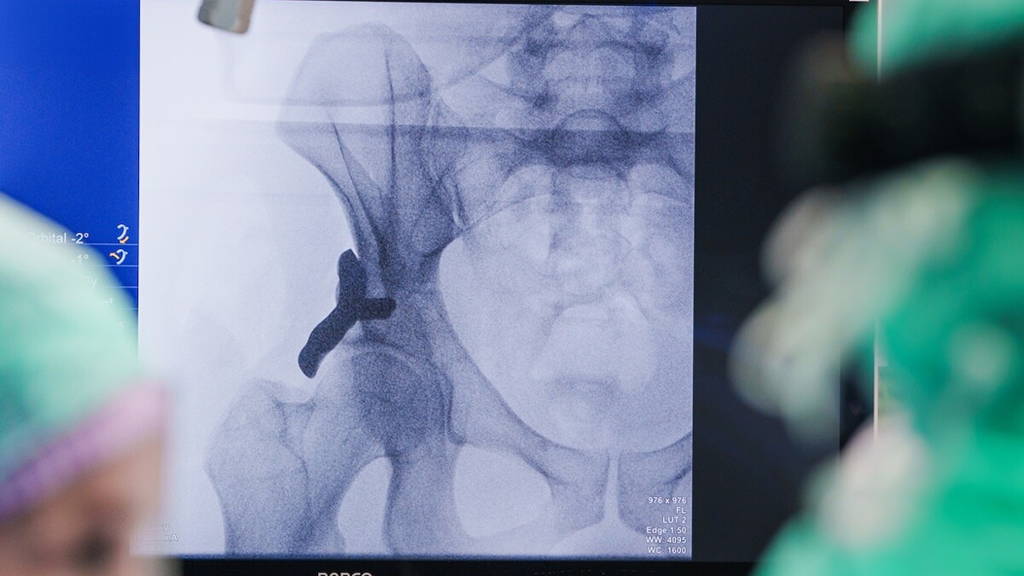

In het Anna Ziekenhuis is in januari voor het eerst ter wereld een op maat gemaakt, 3D-geprint heupimplantaat bij een mens geplaatst. De operatie werd uitgevoerd door orthopedisch chirurg en heupspecialist Rintje Agricola, in samenwerking met het Leids Universitair Medisch Centrum. Met deze ingreep wordt een nieuwe stap gezet in de behandeling van heupdysplasie, een aandoening die zonder tijdige behandeling kan leiden tot ernstige klachten en vroegtijdige slijtage van het heupgewricht.

In het Anna Ziekenhuis is nu een zogeheten safety-trial gestart. In deze eerste onderzoeksfase ligt de nadruk op veiligheid en technische uitvoerbaarheid. De ingreep wordt uitgevoerd bij een kleine groep patiënten, waarbij de uitkomsten zorgvuldig en langdurig worden gevolgd. Het doel is vast te stellen of het implantaat veilig kan worden toegepast en of de techniek technisch betrouwbaar is in de klinische praktijk.